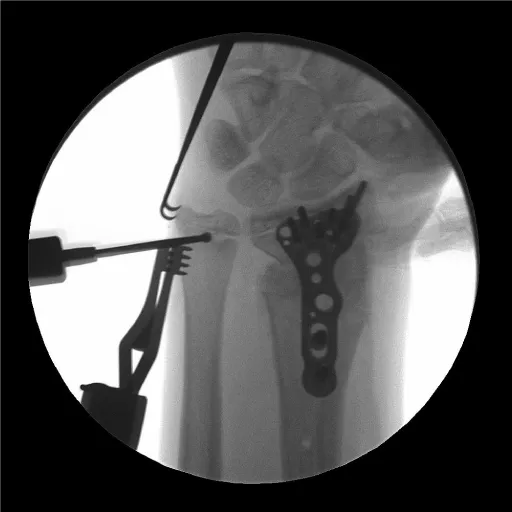

The patient remained immobilized in a short arm cast until 5 weeks post-operatively. At that time, he was taken back to the operating room for Kirschner wire removal. A post-operative splint was placed for one additional week. At that time, radiographs revealed complete healing of the fracture in adequate position and therapy was initiated. At twelve weeks post-operatively, the patient was noted to have full wrist mobility and he was allowed to progress with activity as tolerated. Radiographs revealed complete healing of the fracture and the physis appeared un-affected (Figure 3).

The patient returned two years later due to ulnar sided wrist pain. Clinical examination showed an obvious deformity with a prominent ulna and radial translation of the hand relative to the forearm axis. Radiographs revealed a partial distal radius physeal closure on the radial aspect where the original pins had been positioned. There was a reversal of the normal radial inclination on the frontal film and significant ulnar positive variance (Figure 4). The physis of the distal ulna remained open.